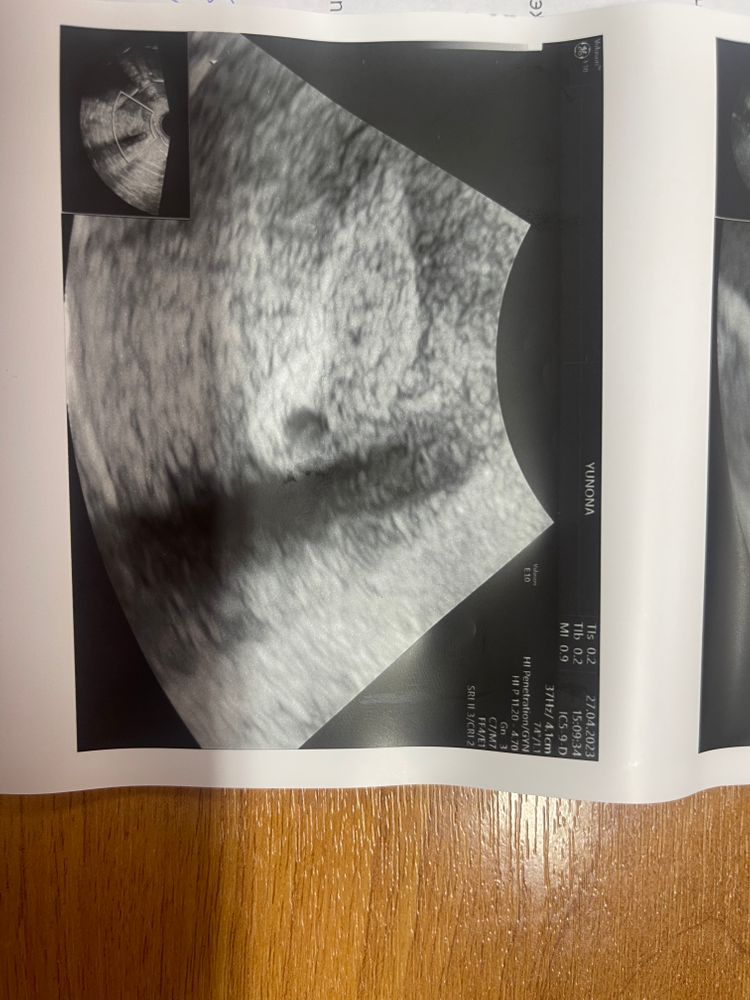

Вопрос в шапке.Была на узи,сказали сгусток крови.А потом добавил надо же как похоже на беременность,но это сгусток крови.Вот я теперь задалась вопросом.Кто в узи разбирается?

Вопрос в шапке.Была на узи,сказали сгусток крови.А потом добавил надо же как похоже на беременность,но это сгусток крови.Вот я теперь задалась вопросом.Кто в узи разбирается?

Можно. При внематочных зачастую есть некое ложное плодное яйцо в матке. Настоящее ПЯ имеет блестящую более светлую оболочку, кровяной сгусток темный без свечения хоть и формой может быть похож. Чисто теоретически можно, но в практике на хорошем аппарате почти исключено. У меня при ВБ был сгусток, изначально описаный как ПЯ под вопросом. На новом узи уже в трубе воспаление

Надежда Шулепова, не поленилась нашла фото. Вот изначально описано как ПЯ со знаком ?, и приглашением через неделю. А

в итоге - сгусток. В трубе внематочная.

Не представляю, как можно спутать сгусток крови и плодное яйцо 🤔 они же по-разному выглядят. Сгусток крови белый, плодное яйцо чёрное.

Эхогенность очень отличается. У вас точно не плодное яйцо.